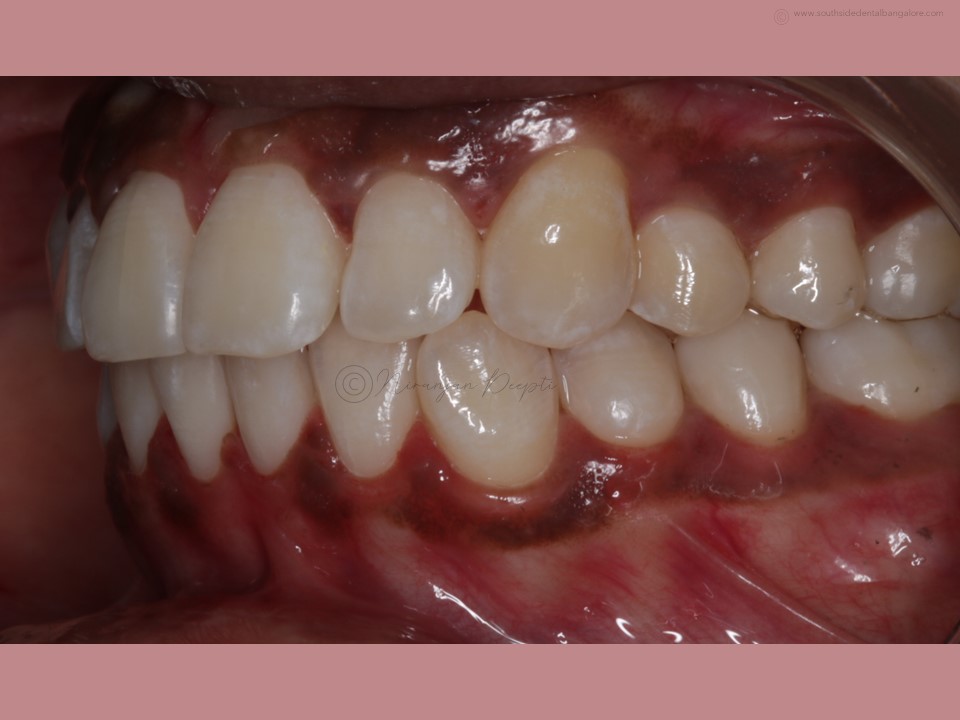

Polishing of teeth after the debonding of braces is a crucial step in the orthodontic treatment process.

- Enhances Aesthetics: Polishing creates a polished, uniform appearance, enhancing the overall aesthetics of your smile and boosting your confidence post-braces.

- Polishing: Using a specialized dental tool, your orthodontist/dentist will carefully polish each tooth surface to remove any remaining adhesive residue and smooth out imperfections.

- Fluoride Treatment: Following polishing, a fluoride treatment may be applied to strengthen the enamel and protect against decay.

- Final Evaluation: Your orthodontist/dentist will evaluate the results to ensure that the teeth are properly polished and free from any residual materials.